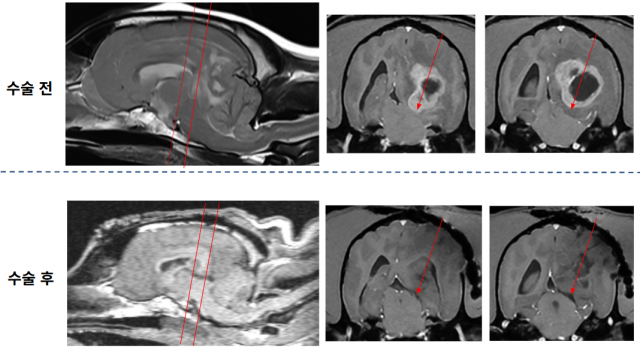

수술 후 1일 차에는 좌측 위협 반사 외 모든 신경학적 기능이 정상화돼 스스로 기립하고 보행할 수 있었으며, 수술 후 2일 차의 뇌파검사에서는 정상 범주의 뇌파 패턴이 재출현했다. 6일 차에는 폐렴도 호전돼 퇴원했으며, 현재는 일상생활에 지장이 없을 정도로 정상적인 신경학적 기능을 유지하고 있다. 수술 후 영상에서 종양이 제거된 것이 확인되며, 종양에 의해 발생했던 뇌간 압박이 해소된 모습이 보인다.